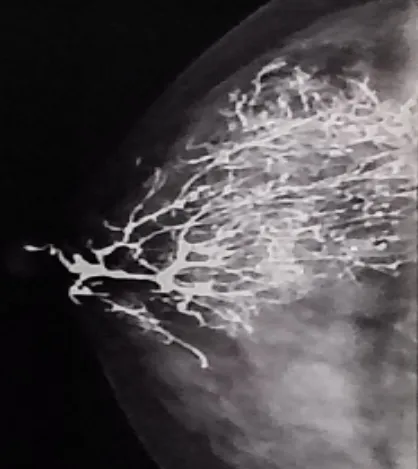

图为正常的乳腺导管造影

我院影像科主任康龙山介绍说,乳腺导管造影是通过将造影剂注入乳腺导管,在X线照射下显示清晰的导管图像,从而判断乳腺内部是否存在异常情况。特别在乳腺癌早期筛查,良、恶性病变鉴别及乳腺结核诊断中具有不可替代的作用。通过该项检查,医务人员可直观评估病变范围及性质,从而为患者制定个性化的诊疗方案。